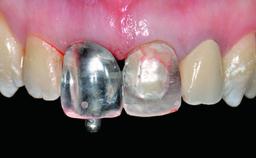

Replacement of a Compromised Upper Right Central Incisor: Hard- and Soft-tissue Augmentation, Late Placement of an RC Bone Level Implant

Abutment Type CAD/CAM

Prosthesis Type FDP

Provisional Implant-Supported Prosthesis Prosthodontic margin > 3 mm apical to mucosal margin Prosthodontic margin > 3 mm apical to mucosal margin